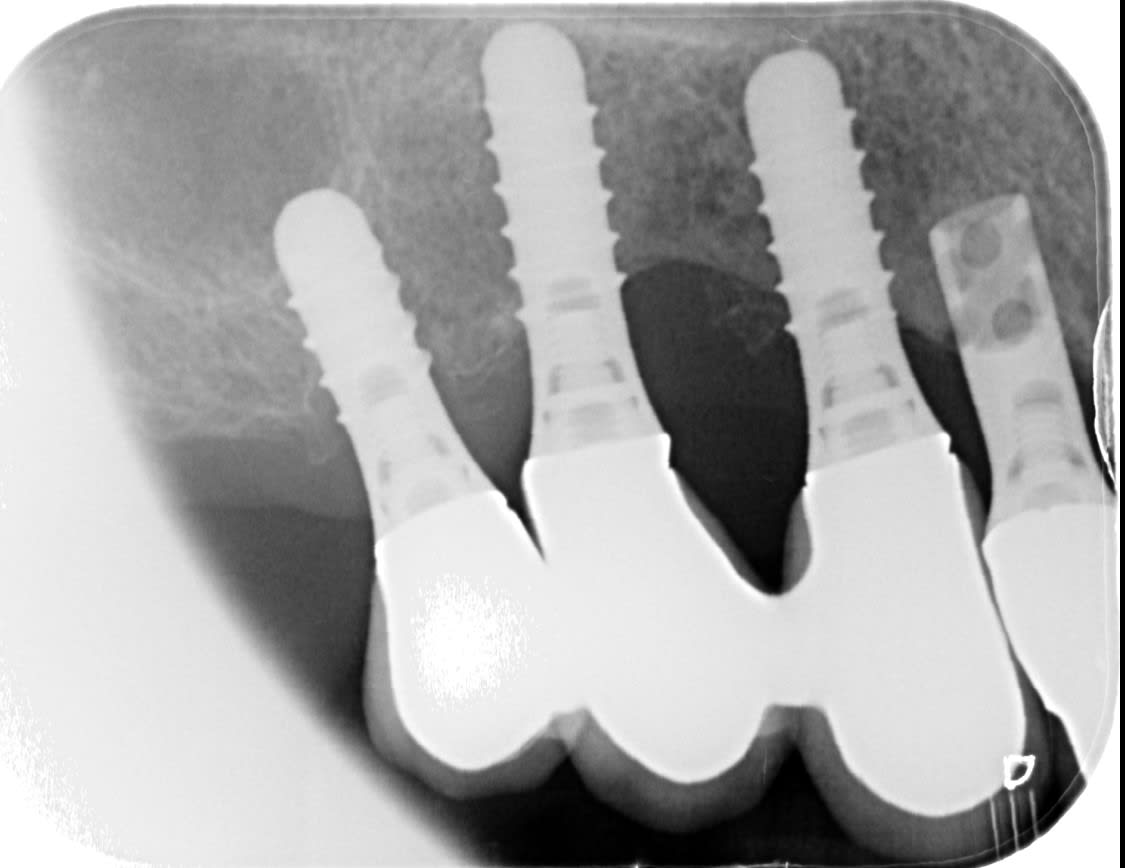

J'ai ces 4 machins posés il y a 20 ans environ, les 3 du fond sont les mêmes on dirait, il ya celui sur la 12 different...

Facile, celui avec plein de trou comme un gruyère c'est un straumann

https://whatimplantisthat.com/implants/details/hollow-cylinder

et les 3 au fond c'est du straumann aussi, mais pas la même gamme

https://whatimplantisthat.com/implants/details/standard-rn